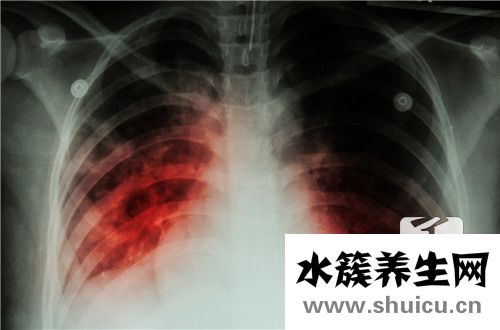

肺結節陰影主要由結核分枝桿菌感染引起,可在檢查時發現。肺結節也是由病毒或細菌感染引起的。肺結節有疲勞、發熱和少量咯血等癥狀。因為兩者非常相似,這種差異已經成為許多人關心的問題。那么,肺結...